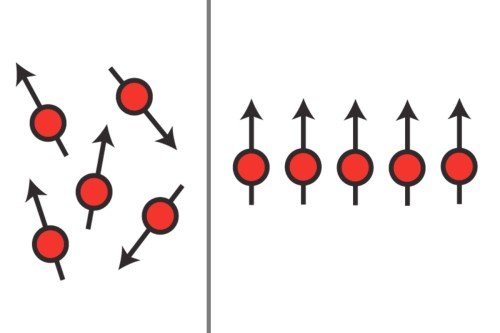

Our researchers have pioneered the use of imaging methods such as PET/CT, MRI, and live microscopy to observe and measure biological processes over time. By highlighting living cells or tissues with specific agents, we use these technologies to aid laboratory investigations into the root causes of cancer and to develop innovative approaches to improve diagnosis and treatment.